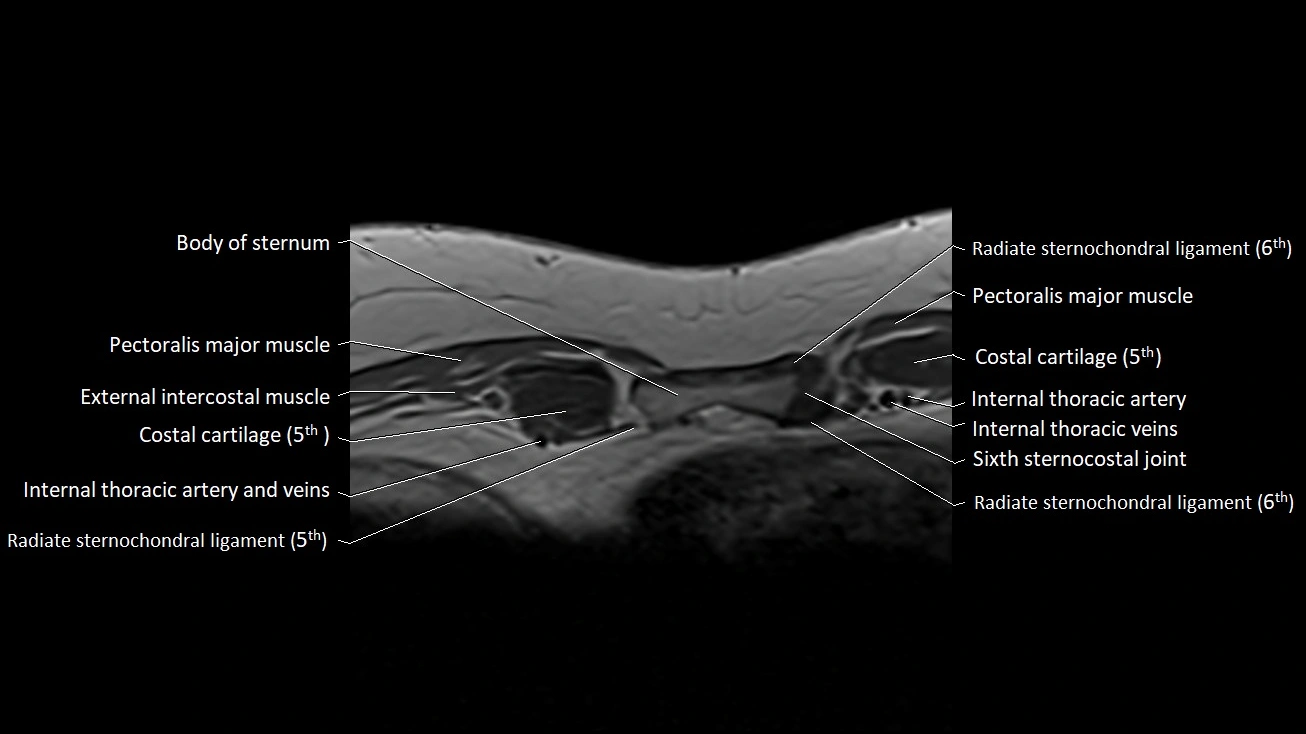

MRI images

image